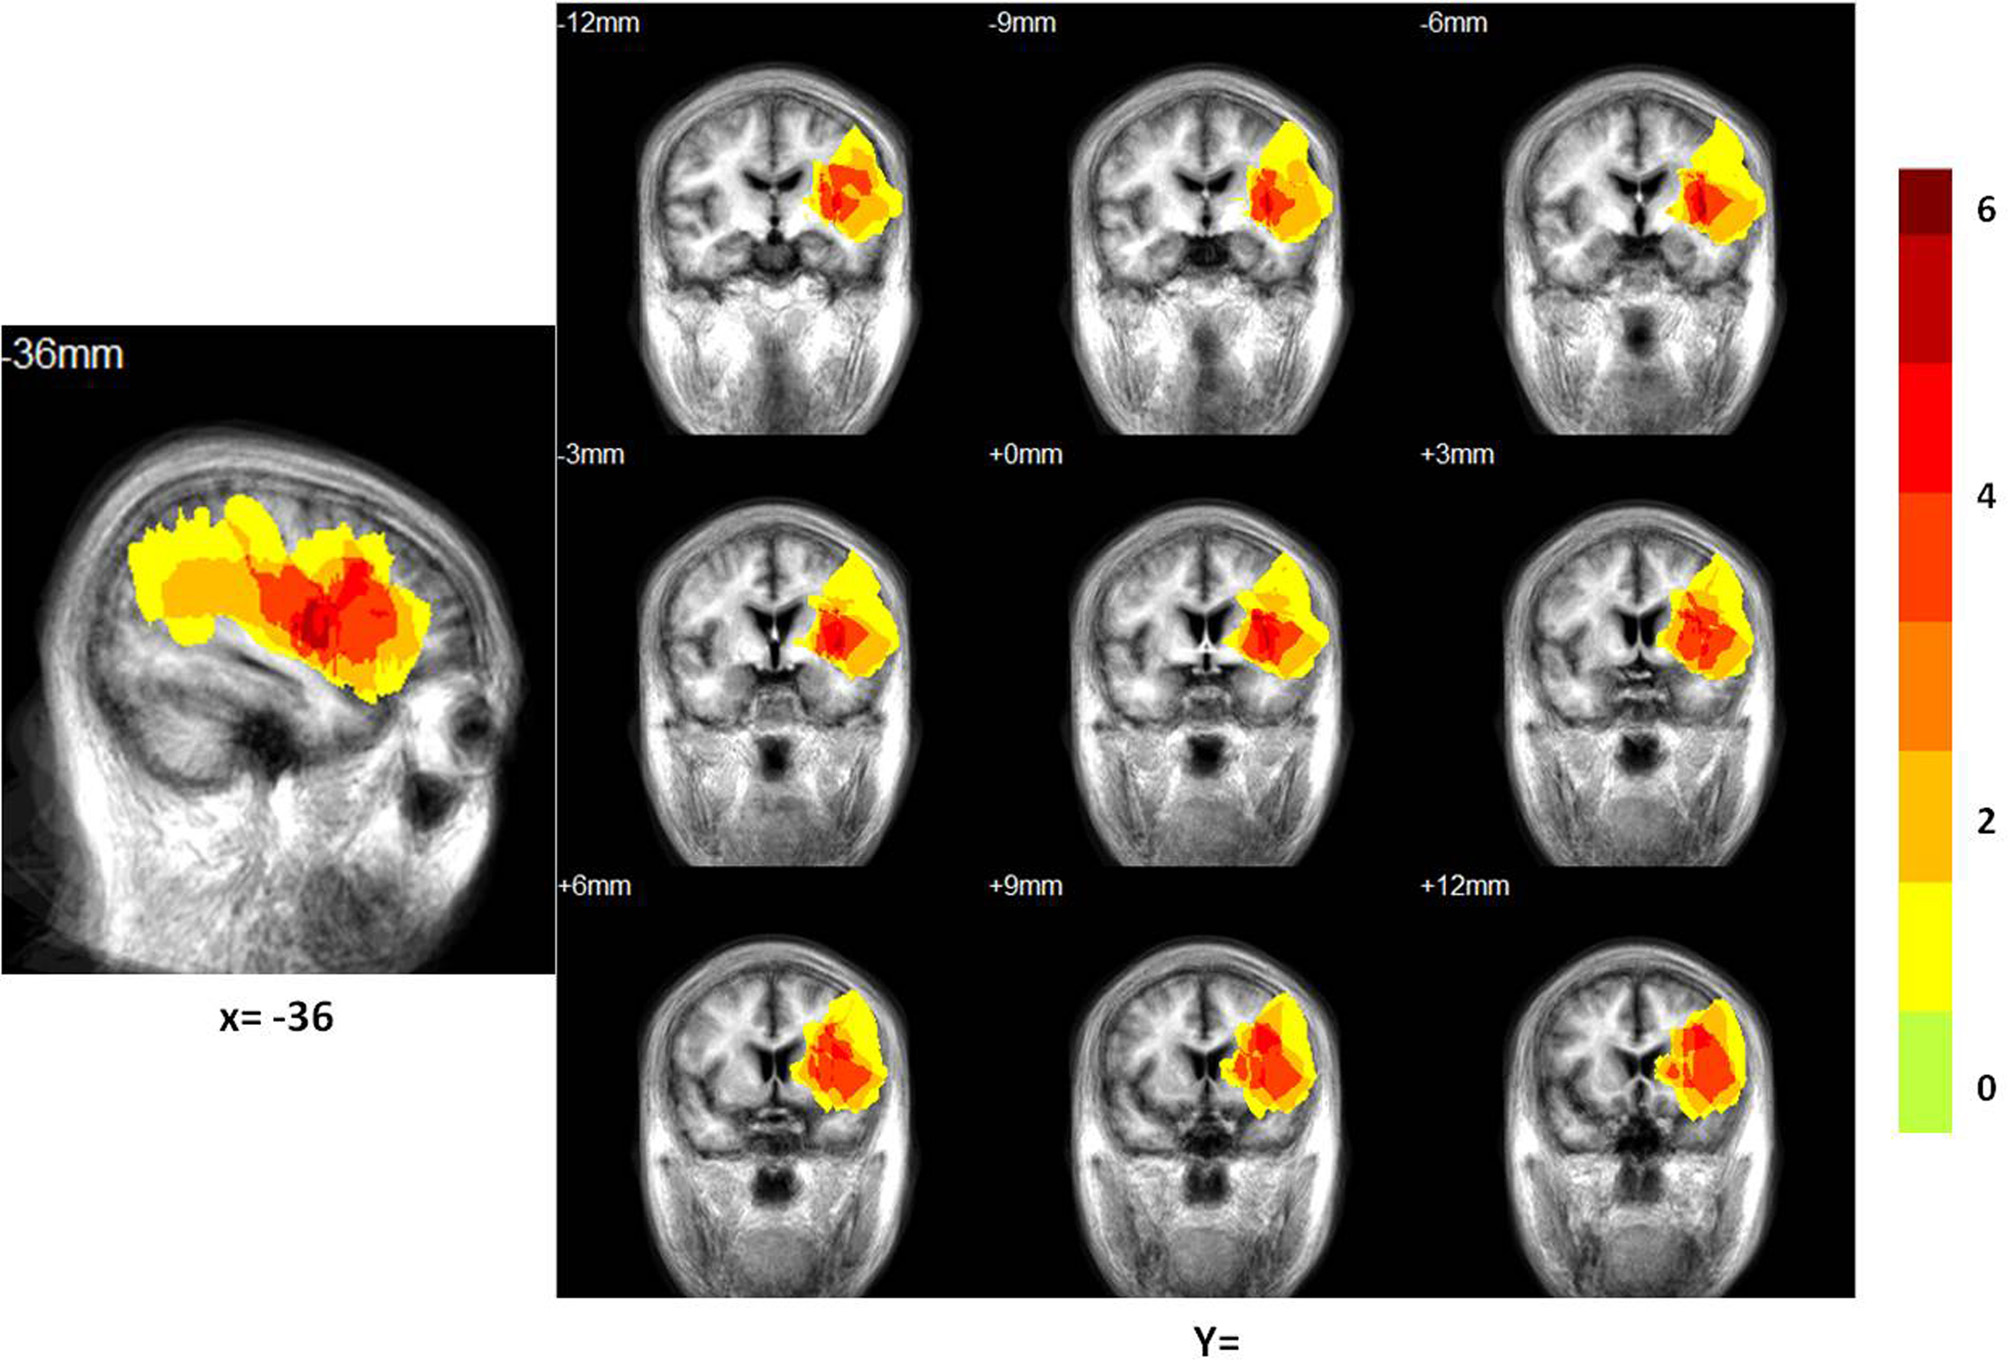

Figure 2

Distribution of the lesion areas of all patients with aphasia, on the average patients' structure brain template. The intensity scale refers to the maximum number of patients with lesions at a particular voxel.

Patient lesion mapping

We constructed a lesion overlap image for all 14 patients. A manually drawn outline of the lesion on the T1 image of each patient was used to overlap on the average structure image using Turtleseg (http://www.turtleseg.org/).

The locations of the patients' infarcts are shown in Figure 2. Of the total 28 subjects (14 patients) enrolled in the study, we dropped one control subject due to technical issues in brain structure and one patient due to failure in the pre-processing of the ICA and network connectivity analysis. We included 13 patients and 13 controls in the ICA and network connectivity analyses. Of all 13 patients, eight patients completed the second scan. Six patients could not participate in the second scan due to their inability to return to the hospital. For characteristics of these patients and scores from all subtests of the CRRCAE, see Table 2.